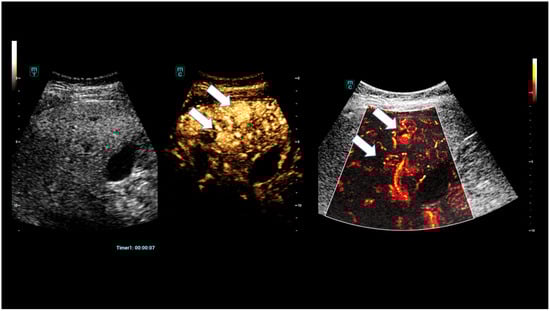

High-Resolution Contrast-Enhanced Ultrasound with SRCEUS for Assessing the Intrahepatic Microvasculature and Shunts in Patients with Hereditary Haemorrhagic Teleangiectasia (Osler’s Disease)

3. Results